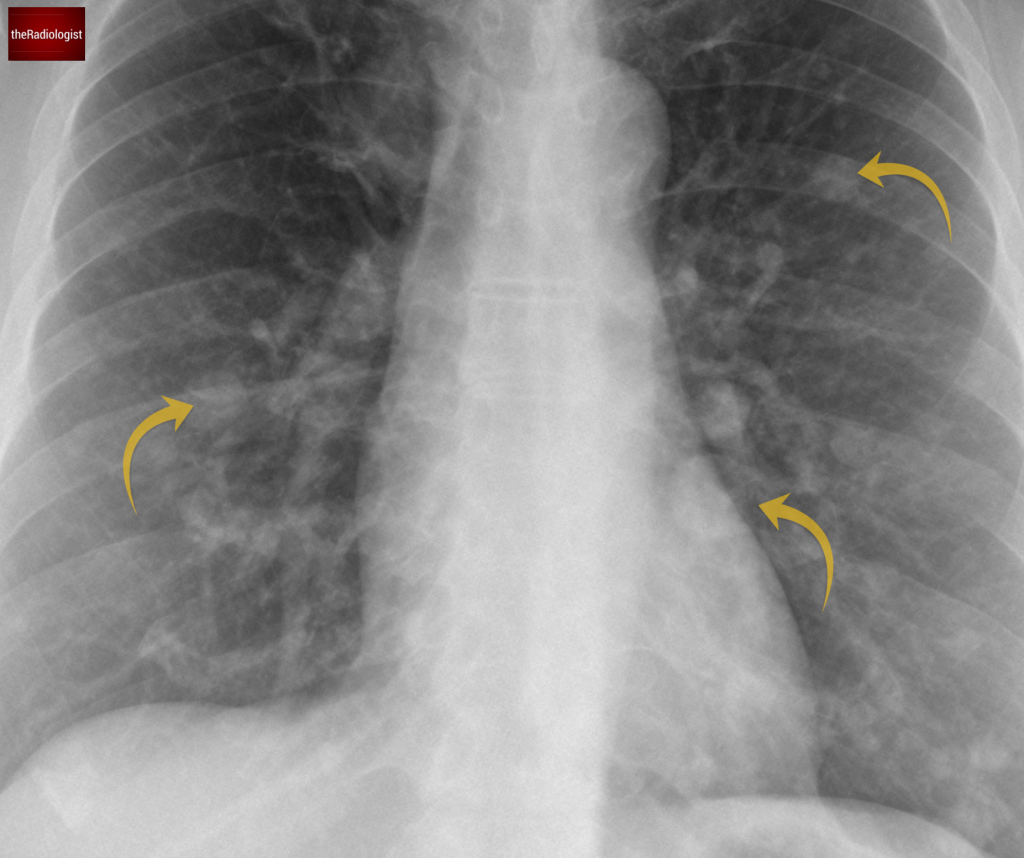

PA view of a chest X-Ray of a female in her 40s

The X-Ray shows multiple lung nodules. On the left, there’s a distinct nodule in the upper zone, and another larger one overlapping the heart border. Moving to the right side, we see a similar pattern, with multiple nodules scattered throughout.

We can see several well defined lung nodules within both lungs.